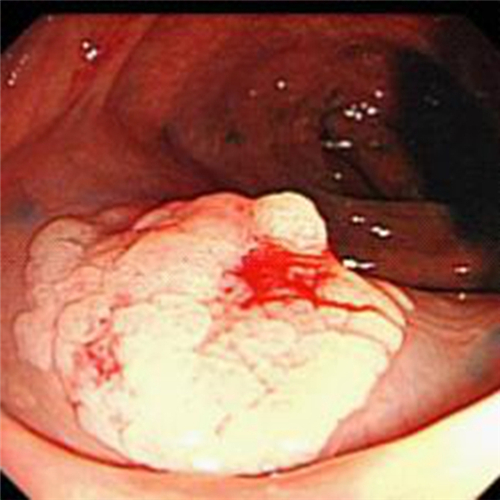

直腸息肉表現

直腸息肉糜爛的